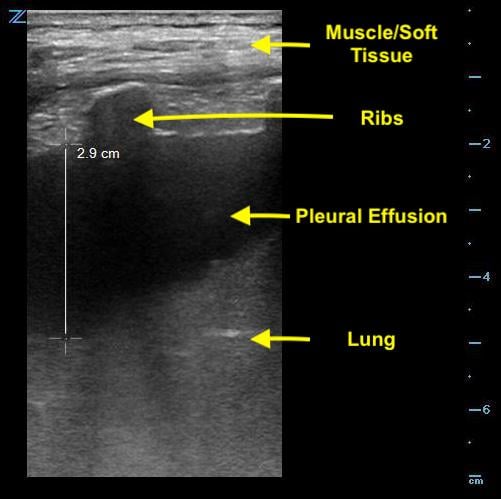

- Look for the deepest pocket of fluid superficial to the lung.

- Freeze the image and take note of the maximum permissible depth of needle insertion; this will prevent puncturing the lung. (Fig. 3)

- Bear in mind that the lung is a moving structure and that the depth of fluid may vary with respiration.

- Figure 3. Measurement of depth to lung parenchyma

- In order to visualize an effusion, the ultrasound beam will first image the chest wall, pleural line and the ribs.

- The edge of bone is echogenic and gives off a characteristic shadowing. (Fig. 4)

- Figure 4. Pleural effusion with rib shadow. The transducer is placed perpendicular to the axis of the rib